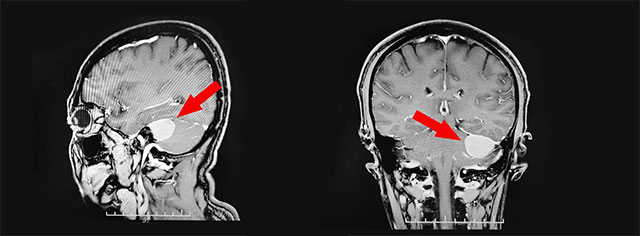

▲ 肿瘤位于左侧桥小脑角区

头颅MRI平扫+增强显示:左侧桥小脑角区可见团块状异常信号,形态不规则,毗邻左侧小脑半球可见受压。神经外科6B病区李士其教授分析指出,根据影像考虑为小脑脑桥角脑膜瘤。由于肿瘤较大,位于颅脑底部,位置较深,且与“生命中枢”脑干毗邻,周围相关颅神经有9条,有非常重要的小脑前下、后下动脉,肿瘤血运丰富,手术难度极大,稍有不慎将带来巨大风险及严重的手术并发症,甚至危及生命!